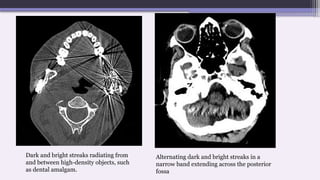

Dark and bright streaks radiating from

and between high-density objects, such

as dental amalgam.

Alternating dark and bright streaks in a

narrow band extending across the posterior

fossa